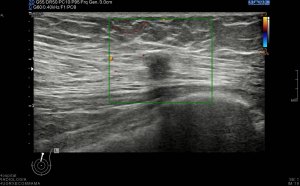

Los vientres anteriores de los músculos Digástricos, que son el objeto del desarrollo de este Post, son dos estructuras musculares redondeadas en el corte transversal, imagen 1, y alargados si los estudiamos en el eje largo, imagen 3, mira:

Ecográficamente los músculos digástricos en eje corto tienen semiología hipoecogénica, en aspecto de noche estrellada, como la de hoy, y en el eje largo en forma de penacho o en forma de plumas con las fibras alargadas y paralelas a la superficie.

Acostúmbrate a mirar esta anatomía en los estudios de cuello sobre todo en pacientes infantiles, por posible localización de adenopatías. En la edad adulta pueden objetivarse cambios de grosor, infrecuentemente, en esta musculatura por diferentes motivos.